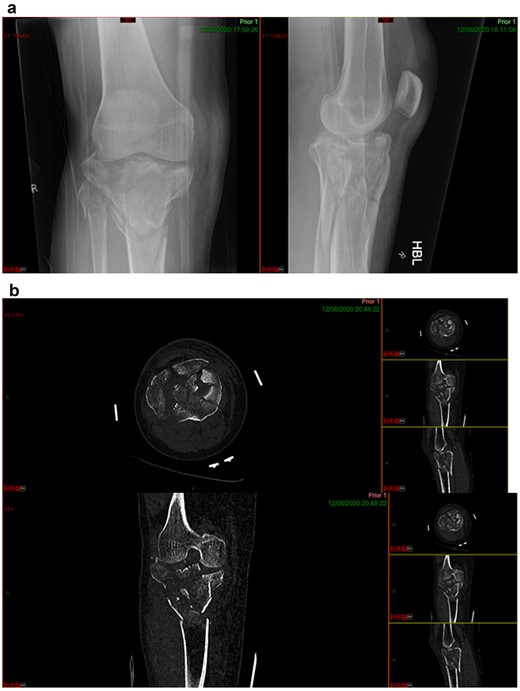

A 68-year-old gentleman who was diagnosed with a Schatzker type VI fracture having fallen 3 m from a ladder (Figs 1 and 2). The injury was closed and neurovascularly intact. The patient was monitored for signs of compartment syndrome. He rapidly developed significant fracture blisters that persisted for over 2 weeks despite regular dressing care. He was deemed too high risk for acute operative intervention because of a high risk of wound complications. Following a multidisciplinary team discussion, he was managed in a cast then a knee brace, mobilising non weight bearing for 12 weeks, at which point the fracture was seen to be healing in a valgus malalignment. The patient was allowed to partially weight bear and received physiotherapy. He was reviewed regularly until fracture had united (Fig. 3). At 8 months post-injury, the patient underwent total knee arthroplasty utilizing a Depuy Synthes (Warsaw, In) PFC Sigma TC3 tibial metaphyseal sleeve and stem, and femoral component without sleeve or stem (Fig. 4). The patient was reviewed post-operatively in clinic at 6 months, the wound had fully healed and the range of motion was 0°–120°. The patient’s pain was significantly reduced, and they were independently mobile. They were kept under annual review and seen at 5 years post-operatively with an Oxford Knee score of 35; the patient used no walking aids and was pain free at rest or during normal walking, with the radiograph demonstrating good osseointegration. The latest follow-up at 8 years revealed no radiographical change in implant (Fig. 5).

CASE 2

This case report follows a 67-year-old gentleman who sustained a Schatzker VI fracture of his right tibia after falling 2 m from a ladder (Fig. 6). The injury was closed and neurovascularly intact; he was managed initially in a neighbouring health board with a bridging external fixator because of the high degree of comminution. He was referred to the current institution; and at a routine review 3 weeks post-injury, it was noted that a pin had fractured. The external fixator was removed, and he was converted into an above knee cast. He progressed to a Sarmiento cast and then a range of motion brace at 12 weeks. Partial weight bearing was permitted, and he received physiotherapy. He was kept under regular review and the fracture had united (Fig. 7); he was noted to have a range of movement of 10°–60° with healed pin site wounds. At 8 months post-injury, he underwent total knee arthroplasty utilizing a posterior stabilised Depuy Synthes (Warsaw, In) Attune revision tibial metaphyseal sleeve and stem, and femoral component without sleeve or stem. The patient had an uncomplicated recovery and kept under routine review in the outpatient clinic. At 6 months’ review, the patient had a range of motion of 0°–105°, fully healed wound and reported a significant improvement in pain. The patient used no walking aids, and the Oxford Knee score was 40 (Fig. 8).